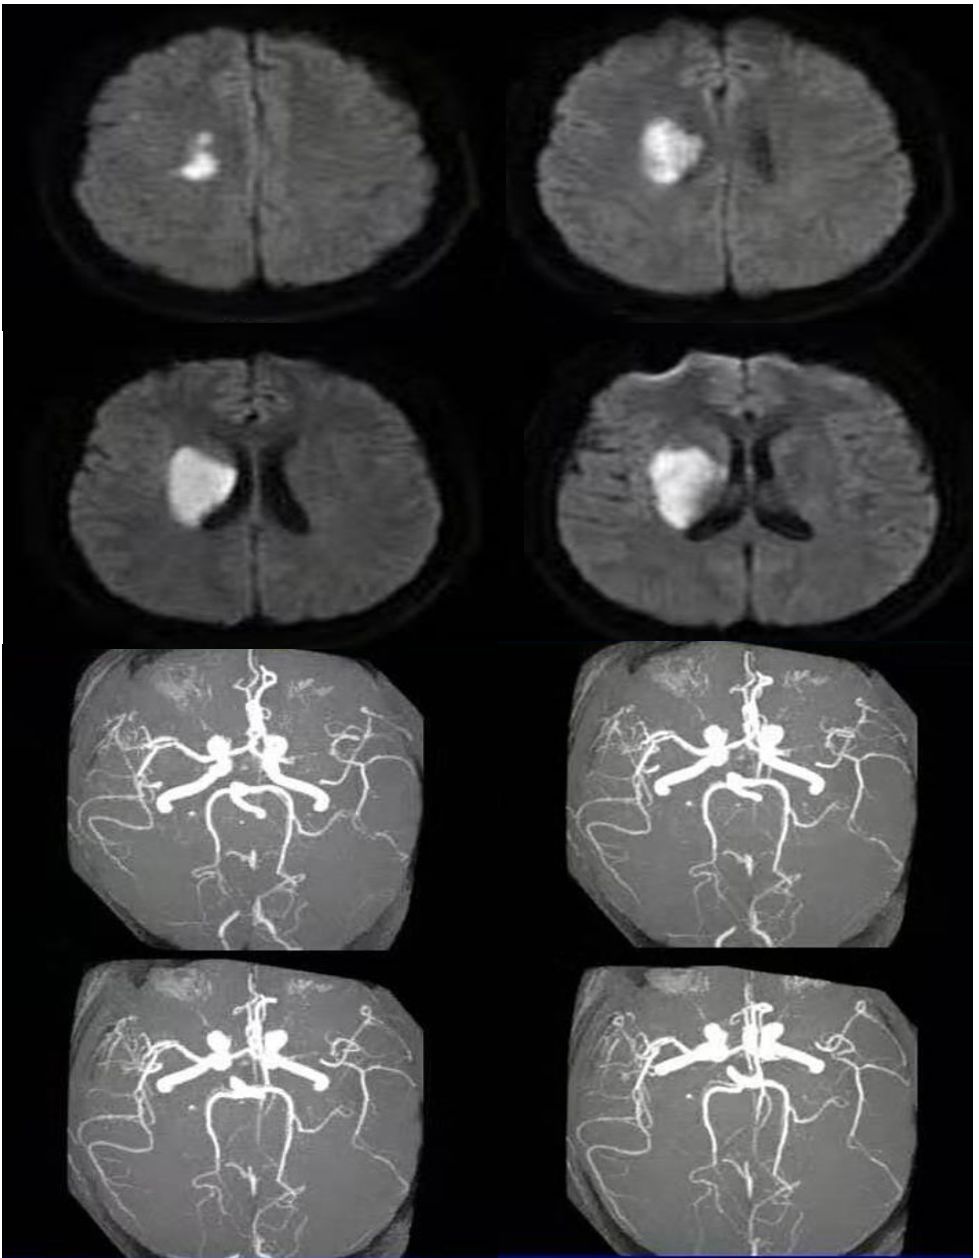

男性67岁,进展性头晕、行走欠稳。影像可见双侧桥臂、脑桥相对对称弥散受限;MRA可见椎基底动脉未见显影。

诊断: 后循环分水岭梗死。

1. 后循环分水岭梗死主要发生在小脑交界区,多位于小脑上和小脑后下动脉之间。

2. 脑干的分水岭梗死常位于脑桥被盖部和基底部连接处的内侧区。

前循环分水岭大家耳熟能详,后循环分水岭可能听起来有点陌生,通过这个病例复习一下相关知识点,遇到类似病例可以推断病因及分型。